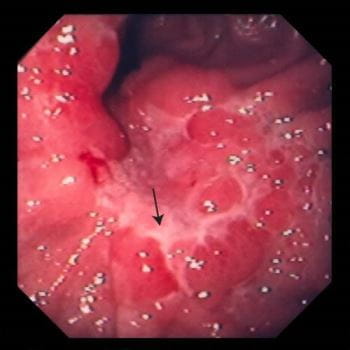

구역질과 구토는 위암의 증상 중에서 많은 이들이 간과하는 부분입니다. 위암 환자들 중 일부는 지속적인 구역질을 경험하기도 하며, 이로 인해 일상생활에 큰 지장을 받을 수 있습니다. 종종 이런 증상은 심리적인 요인이나 다른 소화기 질환으로 오해받기 쉽습니다.

하지만 구토가 반복적으로 발생하거나, 음식물과 함께 피가 섞인 경우 즉시 병원을 방문해야 합니다. 이는 더 심각한 문제의 신호일 수 있으므로 절대 간과해서는 안 됩니다.